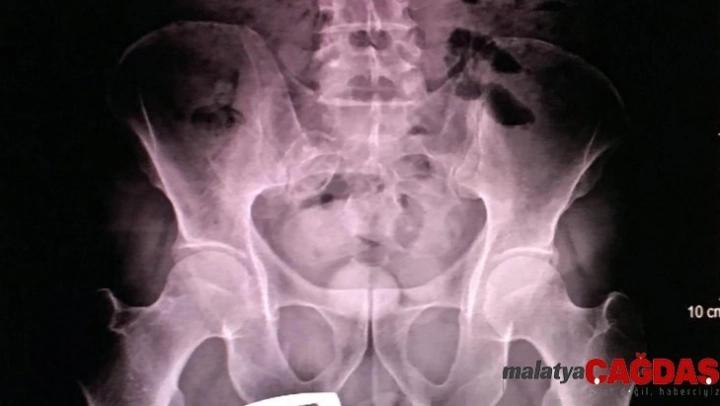

Erzurum Emniyet Müdürlüğü Kaçakçılık ve Organize Suçlarla Mücadele (KOM) Şubesi ekipleri, uygulama sırasında durdurdukları bir yolcu otobüsünde arama yaptı. İranlı B.H.'ye ait olduğu anlaşılan valizde, 21 parçadan oluşan ve 'met' olarak bilinen 607 gram 'metamfetamin' maddesi ele geçirildi. Gözaltına alınan B.H.'nin hareketlerinden şüphelenen narkotik polisi, kendisini sağlık kontrolü için hastaneye götürdüğünde röntgen çekilmesini de istedi. Röntgen filmi sonuçlarında İranlı kadının uyuşturucuyu kapsüller halinde makatına soktuğu anlaşıldı.

Tıbbi müdahaleyle 4 kapsül halinde 96 gram 'met' ve bir kapsülde 28 gram reçine esrar çıkarılırken, uyuşturucunun piyasa değerinin 50 bin lira olduğu belirtildi. İranlı B.H. tutuklanarak cezaevine konuldu.